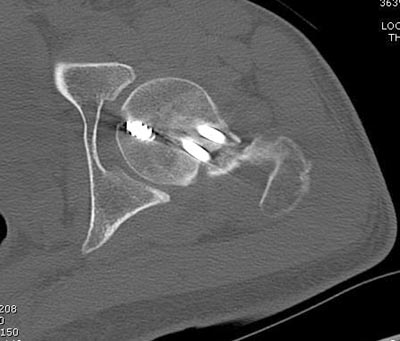

Здесь выставлен ренгенограммы больного, ему 21, травму получил в результате высокоскоростной погони на украденной машине, которая закончилась смертью трех остальных “боевых комрадов”. Начатую коллегой открытую операцию на шейке пришлось закончить мне, установкой винтов и ретроградной фиксацией бедра. Выписка в обычное сроки и наблюдался амбулаторно. Каждый раз напоминали о возможности осложнений ввиде несращения! По истечению 4 месяцев появились признаки варусной деформации. На СТ срезах несращение шейки и бедра. Риминг, замена на более толстый гвоздь и вальгусная остеотомия.

Сразу скажу, что пациент вчера (8.04) прооперирован - артротомия, остеосинтез мыщелков большеберцовой кости канюлированными винтами, открытая репозиция отломков бедренной кости, ретроградный БИОС, остеосинтез надколенника (центральных его отломков) спицами с проволочной петлей. Двухкратная попытка закрытой репозиции шейки на операционном столе после синтеза бедра - абсолютно неэффективна. Учитывая продолжительность и травматичность операции, шейка отложена на 2-й этап. Плечо наверное на 3-й (если вообще делать). Снимки постараюсь предоставить, но чуть позже.

КТ тазобедренного и коленного суставов сделали - картина удручающая, постараюсь выложить.